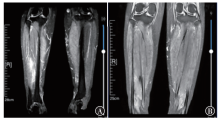

宫颈癌罕见小腿肌间转移1例

宫颈癌肌间转移不常见,小腿肌间转移尤为罕见。现报道1例宫颈癌小腿肌间转移病例。目前针对远处肌间转移的宫颈癌治疗虽无统一的治疗标准,但仍以多学科会诊为主,争取给患者获得更多的治疗选择和生存机会,使患者获益最大化。